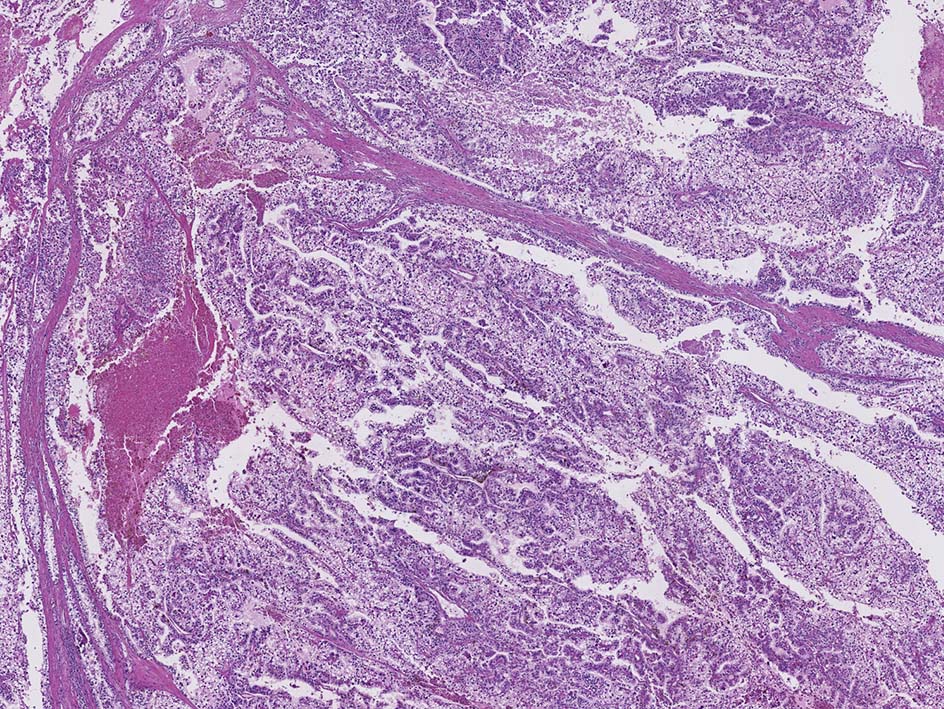

microscopicには線維血管性間質をもち乳頭状または管状乳頭状に細胞が増殖する. 間質にはpsamomaや泡沫細胞の集簇, 硝子化がしばしば認められる.

細胞異型度により1型; 小型立方状, 細胞質は乏しく淡明または好塩基性, 核偽重層はない.核異型はめだたない.(3分類法/FuhrmanでGrade1-2),

2型; 細胞は円柱状で, 不規則な偽重層を呈する. 細胞質は豊で好酸性, 核異型がめだつ(Grade3相当)に分類されている.

1, 2型が混在するときは, 優勢なほうを記載する, 両成分をパーセンテージで表記する考え方があり決まっていない.